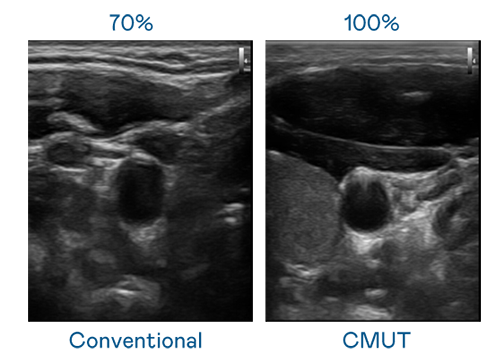

CMUT 技术是一种用电容式微机电元件来产生超音波讯号的技术。与传统 PZT 压电式技术相比,CMUT 频宽增加 30%,更宽频的超音波讯号让影像解析度大幅提升,是实现高影像品质医疗超音波扫描、促进精准医疗发展的关键技术。

超音波影像的解析度高低,首先取决于探头能发出的讯号频宽。AG百家乐官网 CMUT 可提供高清晰的超音波讯号,提供高频宽、高灵敏度、影像纹理细节更高的超音波影像,协助医护人员缩短影像判读时间及利用精准的医疗影像进行诊断。